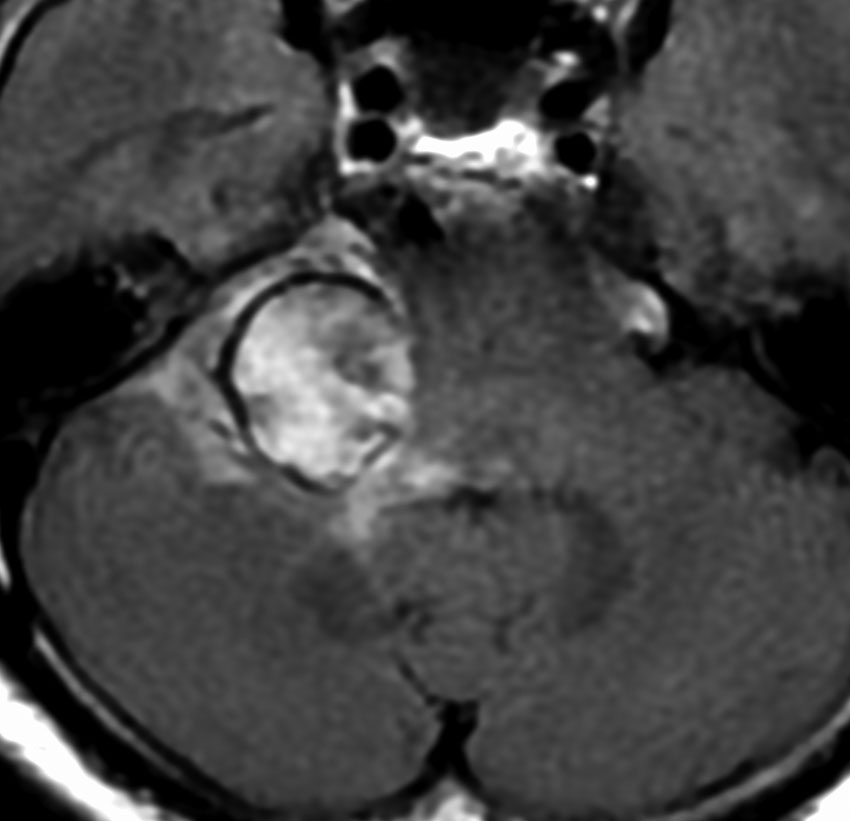

腫瘍が嚢胞性拡大で大きくなって,腫瘍内出血して,閉塞性水頭症になって意識障害を生じた患者さんです。このような事態になると臨時手術で腫瘍を摘出します。

大きなのう胞性聴神経腫瘍です。いくつかの袋が重なって腫瘍を形成しています。橋や延髄(脳幹部)が変形して,第4脳室がつぶれて閉塞しています。袋の周りが白く線状に造影されているのですが,この袋の壁だけに腫瘍細胞がありますから,これを剥がすように摘出します。顔面神経が薄くなって袋の壁にくっついているのですが,袋を破ってくしゃくしゃにすると顔面神経の位置が変わってしまって,顔面神経を損傷することがあるので要注意です。のう胞性聴神経腫瘍の方が顔面神経麻痺の後遺症の頻度が高いという報告もあるくらいです。この患者さんは迷走神経と舌咽神経の圧迫も強くて,ご飯を飲み込むことが難しくなっていました(嚥下障害)。

また,この患者さんは急に容態が悪くなって意識障害となりました。何故なら腫瘍の内部で出血したからです(黄色の矢印の部分)。第4脳室が詰まって閉塞性水頭症になって側脳室が拡大しています(右の画像)。